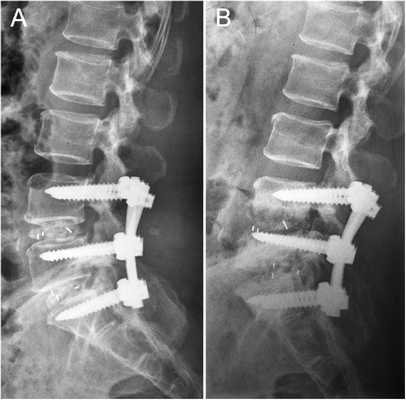

Стабилизация поясничного отдела.

Показаниями к вживлению ригидных конструкций транспедикулярной фиксации, в том числе и Krypton®, служат практически все случаи позвоночной нестабильности:

- выраженный листез позвонков;

- травмы позвоночника (вывихи, переломы и пр.);

- спинальные новообразования;

- дегенеративные патологии, сопровождающиеся неврологическим дефицитом, например, межпозвоночные поясничные грыжи; и кифоз;

- несостоявшийся артродез;

- последствия неудачно выполненных вмешательств и др.